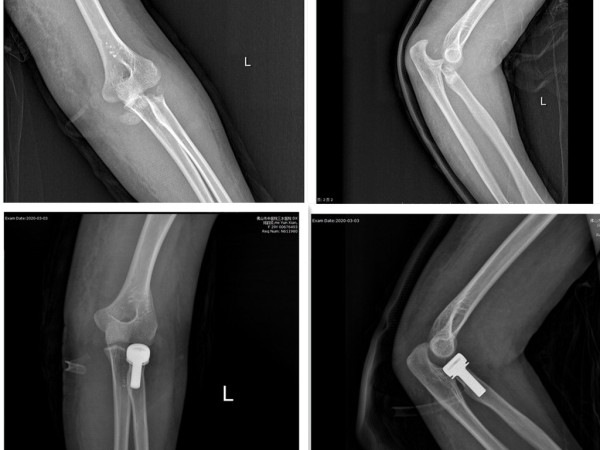

2019年,在广东省中医院的许树柴教授指导下,顺利完成我院首例膝关节单髁置换手术(UKA技术),2015年谢学文主任率先我科开展运用MIPO技术结合中医正骨手法微创治疗四肢干骺端骨折。继而,李伟强主任开展小儿陈旧性孟氏骨折矫形内固定术、截骨矫形支架外固定术、胫骨近端高位截骨矫形手术(HTO技术)、桡骨头置换术及骨搬运技术等。近年,在涂泽松主任指导下,更开展了肩关节置换术及进一步改善支架矫形技术。为我院创伤骨科矗立一座座里程碑。

目前,科室基本形成以四肢创伤骨折(闭合骨折、开放骨折、内固定取出等)、小儿骨骼创伤及创伤后遗留畸形(小儿肘部骨折及畸形,膝关节发育性畸形,踝部创伤后畸形)、四肢筋伤(软组织损伤及膝、踝关节侧副韧带损伤)、膝关节骨性关节炎中符合“保膝”治疗的患者、骨病(骨质疏松症、急慢性骨髓炎等)、脊柱疾病(胸腰椎单纯性压缩性骨折、腰椎间盘突出症、颈椎病)以及胸部创伤(肋骨骨折及稳定型胸部挫伤)七大重点为核心的发展方向。

对临床上不稳定型、复杂型四肢创伤骨折,运用“AO”、“BO”理念,施行闭合/切开复位钢板、髓内钉内固定术,对临床上开放性骨折施行清创复位内固定+支架外固定术;对临床上骨不连、骨缺损病例,施行切开植骨内固定/支架外固定术;对肘、腕、踝关节脱位合并骨折,运用有限切开复位克氏针内固定+胯关节外固定支架(可活动型),运用MIPO技术结合锁定钢板内固定治疗对四肢干骺端骨折进行微创治疗,运用单髁置换及HTO技术对膝前内侧骨性关节炎进行“保膝”治疗,运用桡骨小头假体置换治疗肘关节恐怖三联征;对开放性骨折脱位病例施行清创复位胯关节支架外固定术,有效降低肢体的感染率及伤残率。